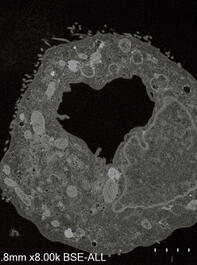

COVID-19 virus. microscope images. From the book Virus. 2020.

© Antoine d'Agata/Magnum Photos

VIRUS. Book. 2020.